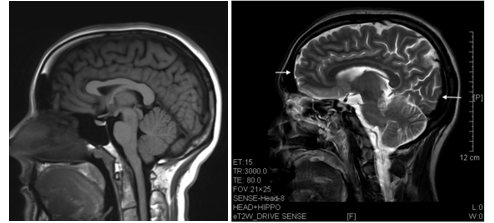

The brain is heavily affected by prolonged ketamine use, in most cases it destroys multiple regions of the brain. According to Chunmei Wang of the Brain Research Center, Institute of Chinese Medicine “the brain regions affected were prefrontal, parietal, occipital, limbic, brainstem and corpus striatum. The lesions affected both the gray and white matter” (5). (see fig. 2).

Fig. 2. The left shows a normal brain with no drug abuse. The right is an addicts’ brain who has done a half gram of ketamine each day for seven years. You can see that some sections of the brain almost looked smashed or caved in, this is where it has deteriorated from the usage of ketamine from Chunmei Wang et al.; “Brain damages in ketamine addicts as revealed by magnetic resonance imaging”; Frontiers in Neuroanatomy, vol. 7, no. 23, 2013; pp. 1-6